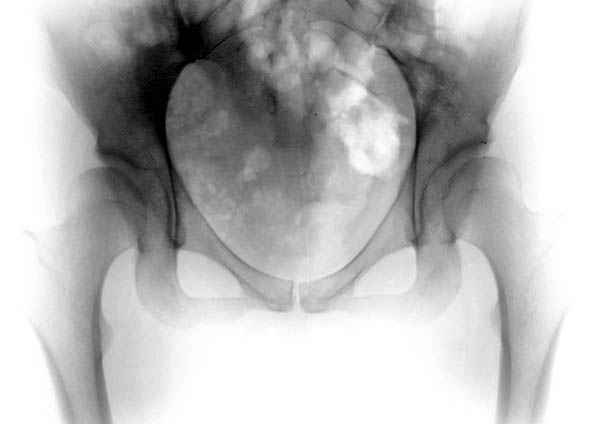

Картина типичной эволюции дисплазии сустава "кистовидная перестройка", на фоне неправильного взаймоотношения сустава "да тут угол Виберга 0 градусов" на вершине наибольшей нагрузки в вертлужной впадине образовался участок разрежения, "киста", в последующем через этот участок образуется перелом - стадия фрагментация дисплазии.

Для установки диагноза достаточно информации, на рентгенограмме передний и задний край ацетабулум образовали перекрест, "цифру восемь", указывающий на небольшую ретроверсию, а суставная щель одинаковой ширины на всем протяжении, что доказывает, что с покрытием хряща проблем нет. Головка бедра покрыта всего наполовину, это явное нарушения взаимоотношений.

"Однако до 39 лет у пациента не было болей в суставе, и он возможно не знал о наличии у него дисплазии"

Правильно, многие в молодом возрасте не подозревают о наличии диспластических явлений, болезнь начинается с боли в суставе, особенно у женщин в третьей декаде жизни после замужества и беременности, когда набранный вес давит на сустав, а у мужчин набранный вес за короткое время приводит к ухудшению взаимотношений в суставе.

"Второй сустав у него не болит, хотя в течение последнего года он нагружает его "за двоих"

Долго работать “за двоих” не будет, скоро начнутся проблемы со вторым суставом, и поэтому рекомендуется срочная операция, который спасет второй сустав.